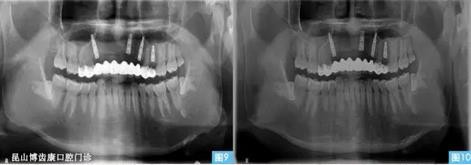

圖9圖10:(左圖9)術(shù)后3個月,(右圖10)術(shù)后6個月。